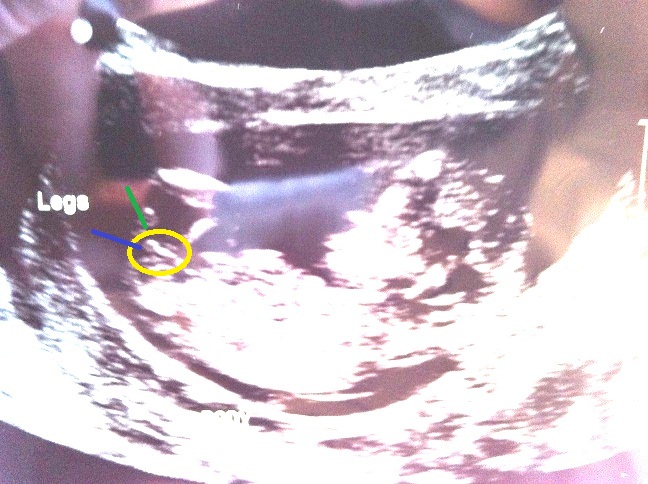

Attachment 3559

This is what I see.... See the top blob where the green line is pointing and then underneath the blue line there is another section of blob? I had this on mine and he is all boy! My girls however had two vertical lines stacked on top of each other no blobby bits like this ;)

Attachment 3560

This is my boy just for comparison!

Yes I see! They do look very similar.....To me it does look like a little penis & it has done since I came across the nub theory....My DD's nub was perfectly straight with two perfectly visible lines parrallel to each other, if that makes sense?